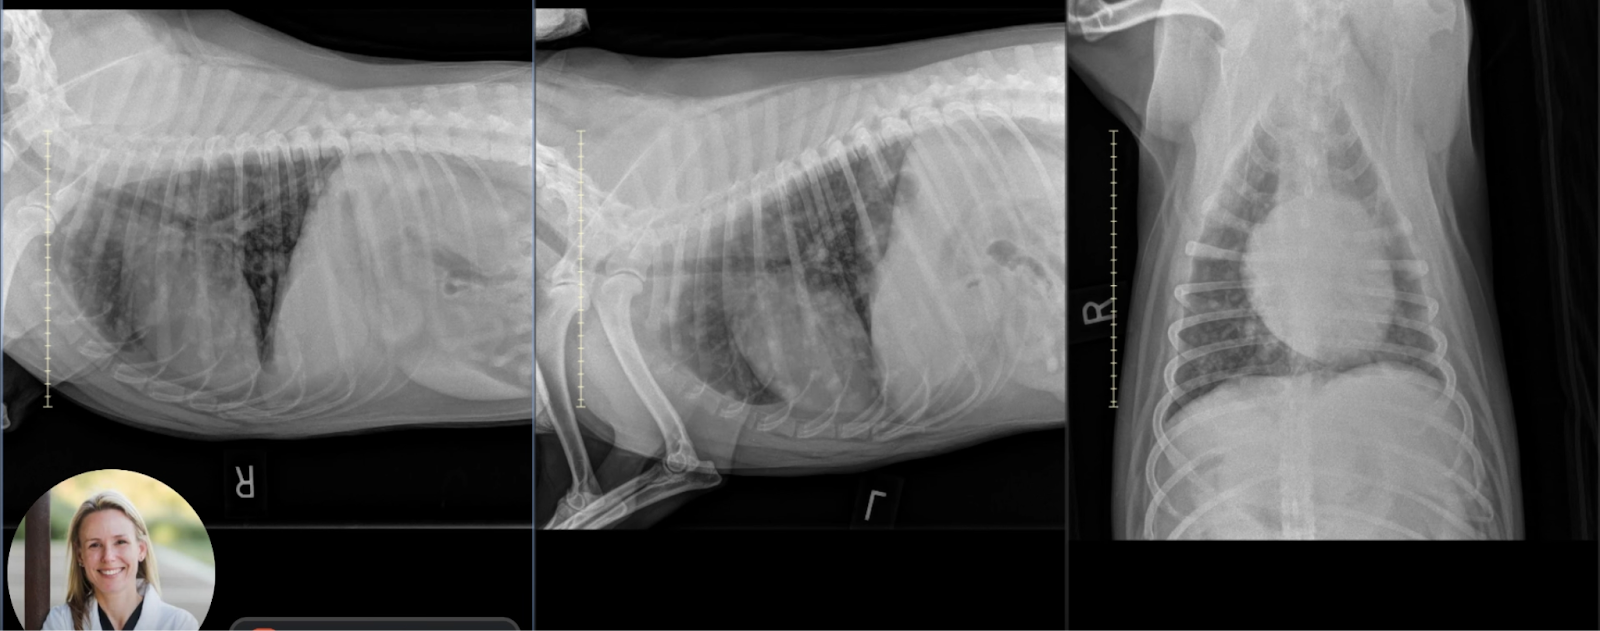

Right lateral thoracic radiograph of Australian Cattle Dog with multifocal soft tissue nodules in all lung lobes, consistent with metastases.

Image 2: Right Lateral View

• Nodular Pattern: Numerous soft tissue opaque nodules are clearly delineated. The largest visible nodule is approximately 1.4 cm in diameter. Distribution is multifocal and involves all lung lobes.

• Pleural and Mediastinal Evaluation: No pleural effusion, pneumothorax, or intrathoracic lymphadenopathy is evident. The cardiac silhouette and musculoskeletal margins appear normal.

Left lateral thoracic radiograph of Australian Cattle Dog confirming widespread pulmonary nodules typical of metastatic disease.

Image 3: Left Lateral View

• Confirmation of Lesions: The soft tissue nodules identified in the right lateral and VD views are reaffirmed, solidifying the diagnosis. Again, there is no effusion or lymph node enlargement.

Composite image of thoracic radiographs from an Australian Cattle Dog with pulmonary metastases, alongside Dr. Sage reviewing the case

Dr. Sage reviews the full set of thoracic radiographs in the link below, highlighting how each view contributes to confirming pulmonary metastatic disease.